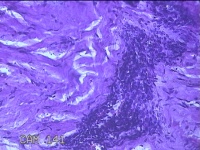

右侧前臂结节

性别

女

年龄

38岁

临床诊断

皮下结节

一般病史

发现右侧前臂结节1年余。

标本名称

大体所见

灰白粉红色带皮肤样组织0.8x0.7x0.3cm一块,表面带梭形皮肤0.8x0.7cm,皮下见结节0.8x0.5x0.3cm一个,切开结节呈实性,切面灰白粉红色,质软。